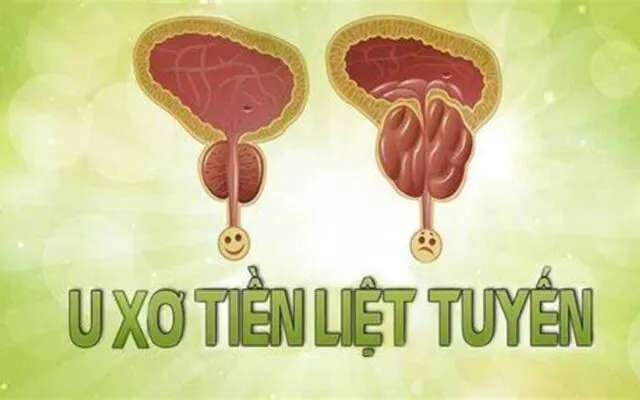

U phì đại tuyến tiền liệt: Cách điều trị

U phì đại tuyến tiền liệt là một vấn đề sức khỏe phổ biến ở...

U tuyến tiền liệt là gì?

Sức khỏe nam giới, đặc biệt là khi bước vào độ tuổi trung niên, luôn...